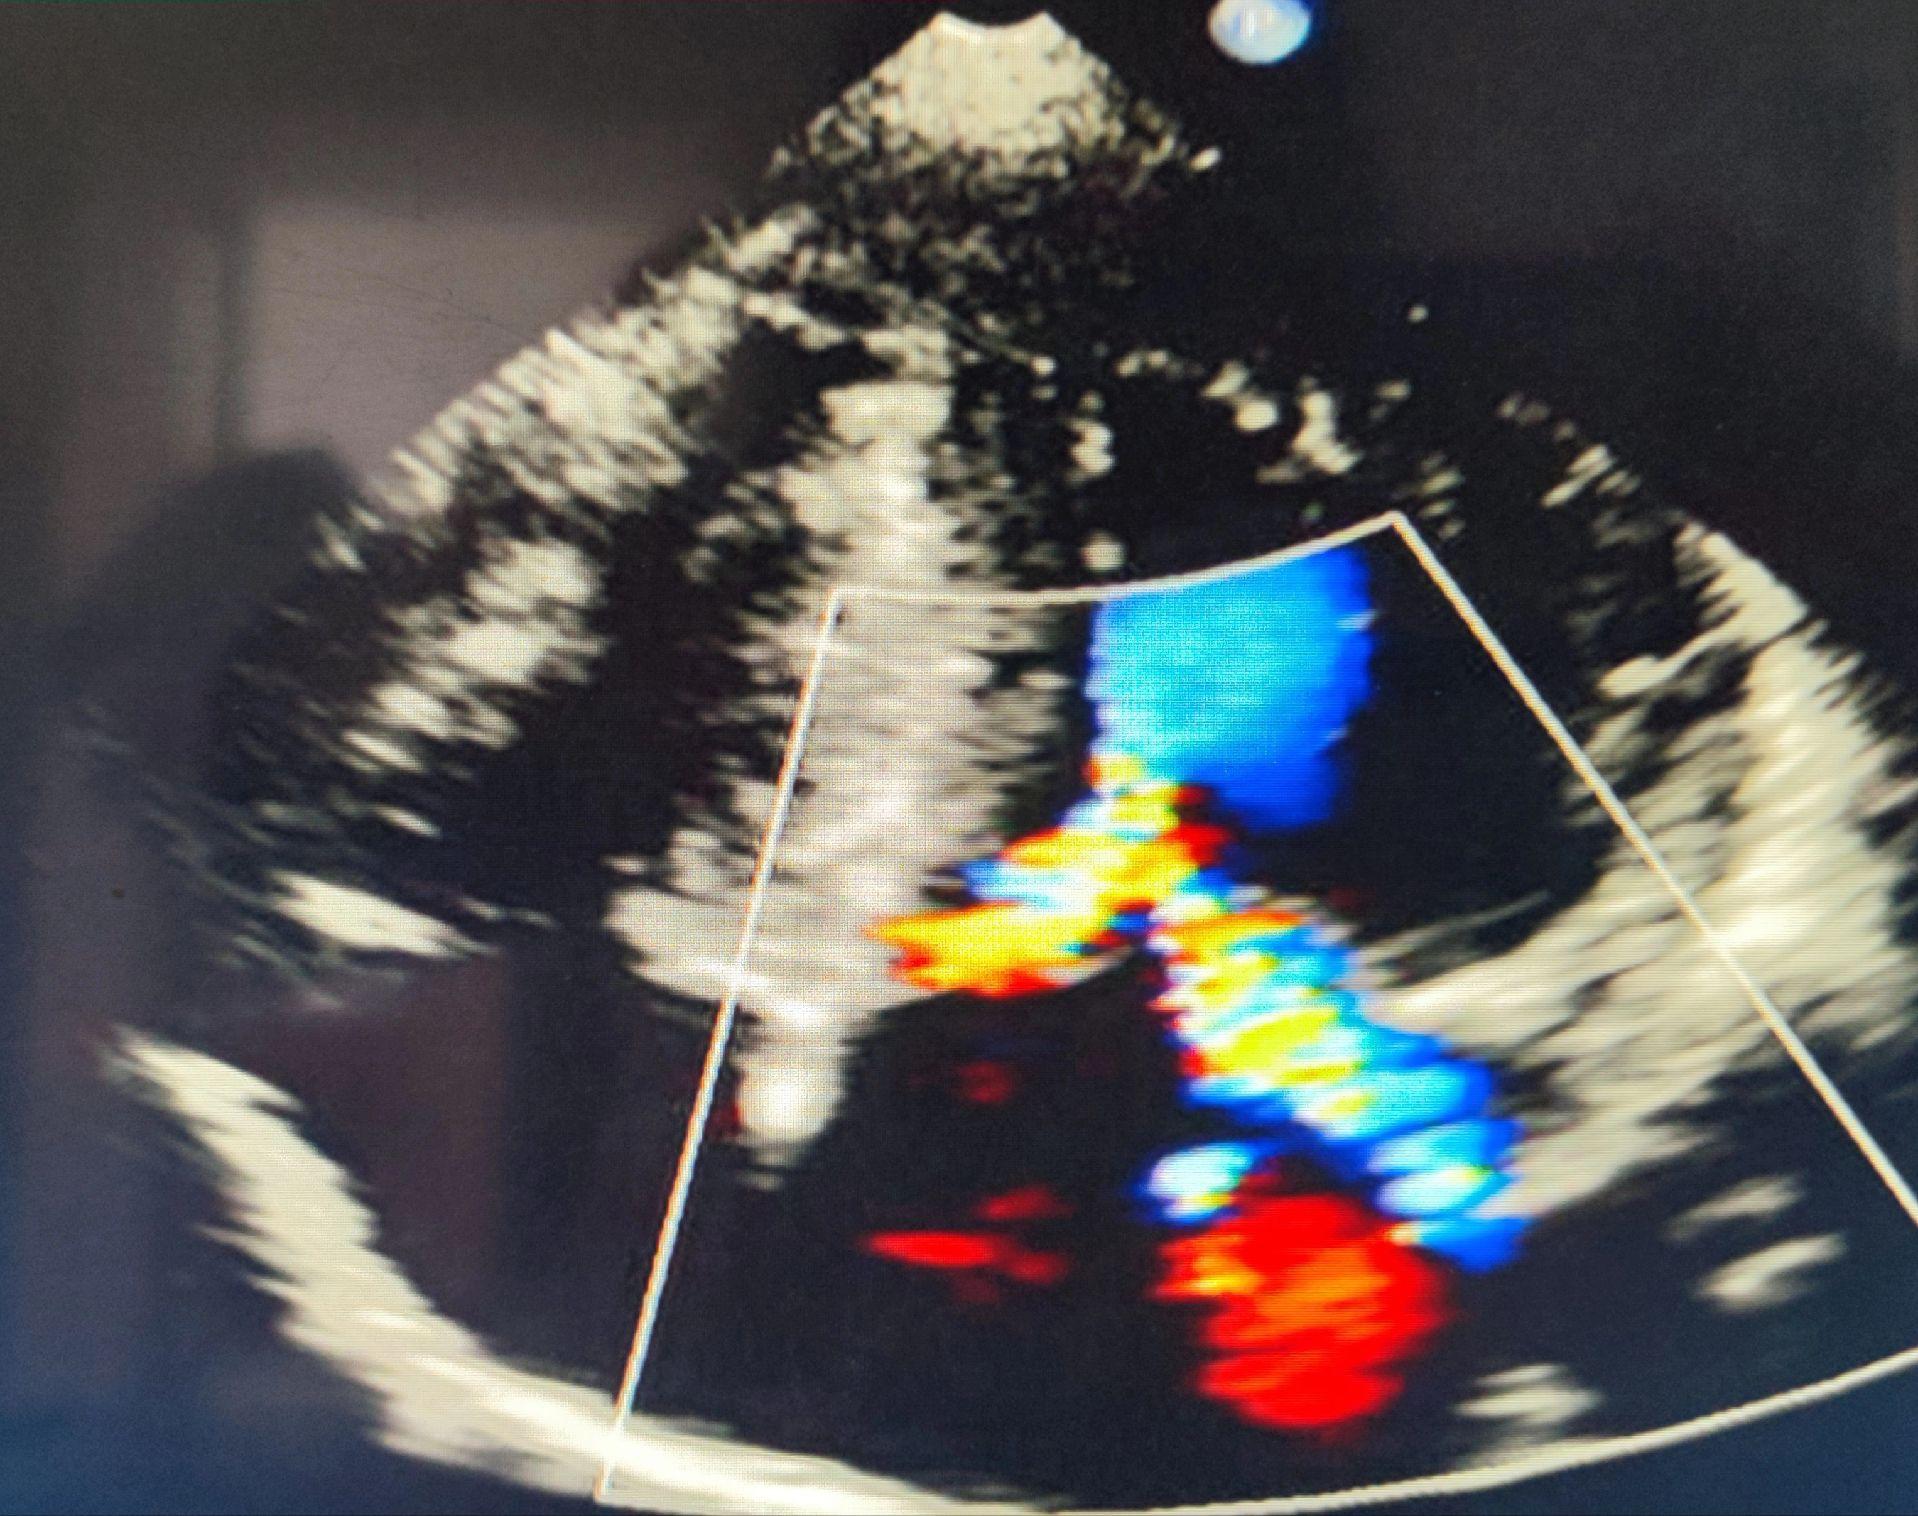

梗阻性肥厚型心肌病。家族性者为常染色体显性遗传 女,44岁,体检发现 SAM现象 左室流出道频谱匕首样 已手术